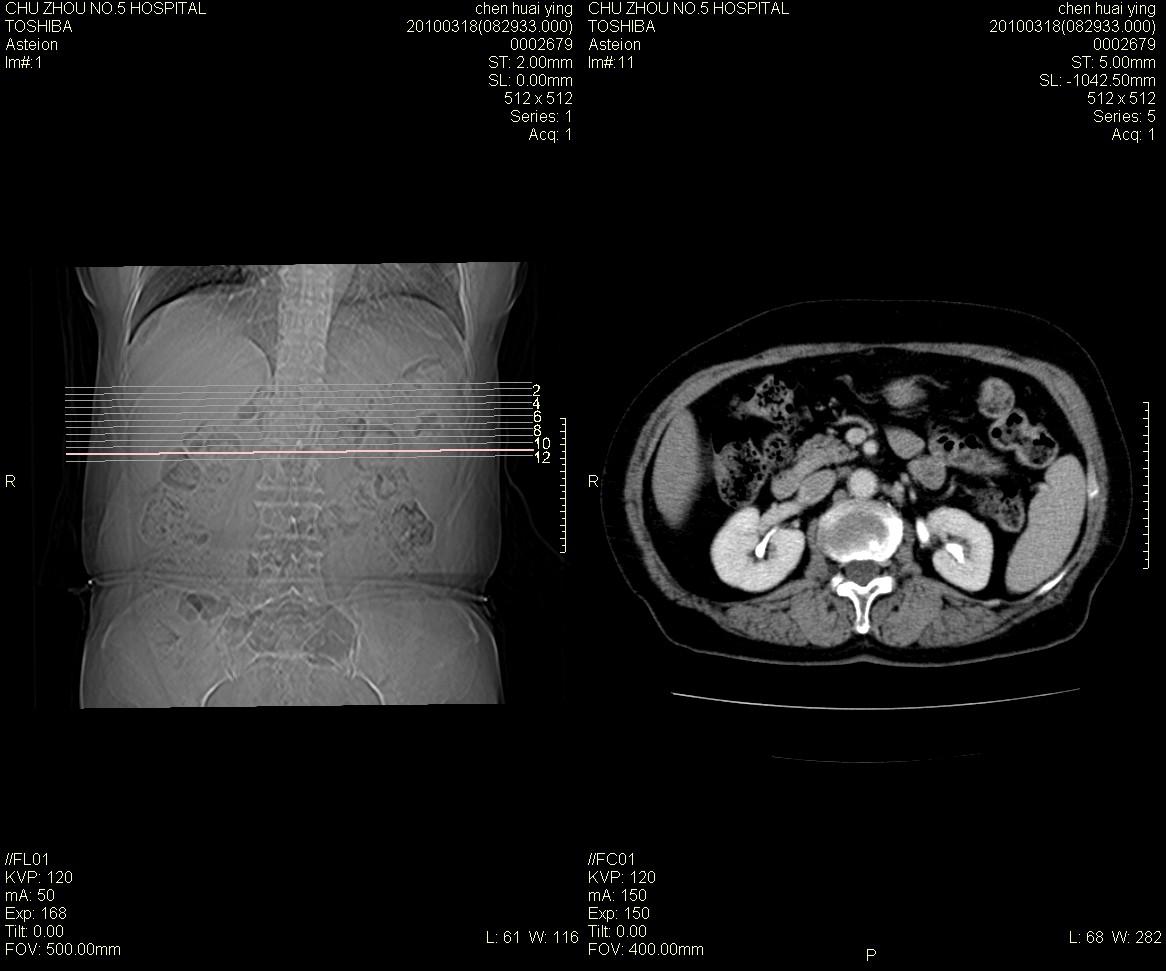

标题: CT25148 肾上腺增强

ct25148增强图片

动脉期太早了,扫的有点低。考虑良性占位右侧肾上腺嗜铬细胞瘤并坏死囊变可能性大,神经鞘瘤不排除。

右侧肾上腺占位性病变,病人是否有高血压?嗜铬细胞瘤?

右侧肾上腺嗜铬细胞瘤并坏死囊变可能性大

考虑双侧肾上腺肿瘤性病变。